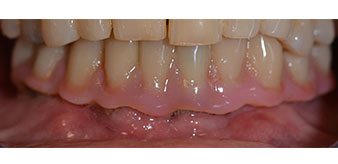

La paziente, 64 anni, presenta una dentatura residua di denti 38, 33 e 43 e una protesi combinata innestata nella mandibola (Fig. 1 e 2).

dentatura residua

Fig. 1

Fig. 2